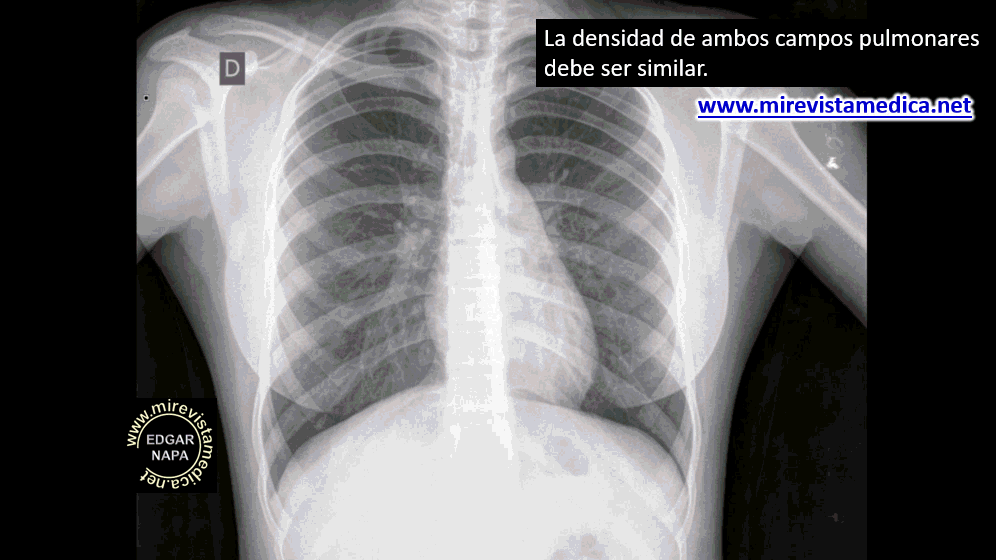

RADIOGRAFÍA (Rx)